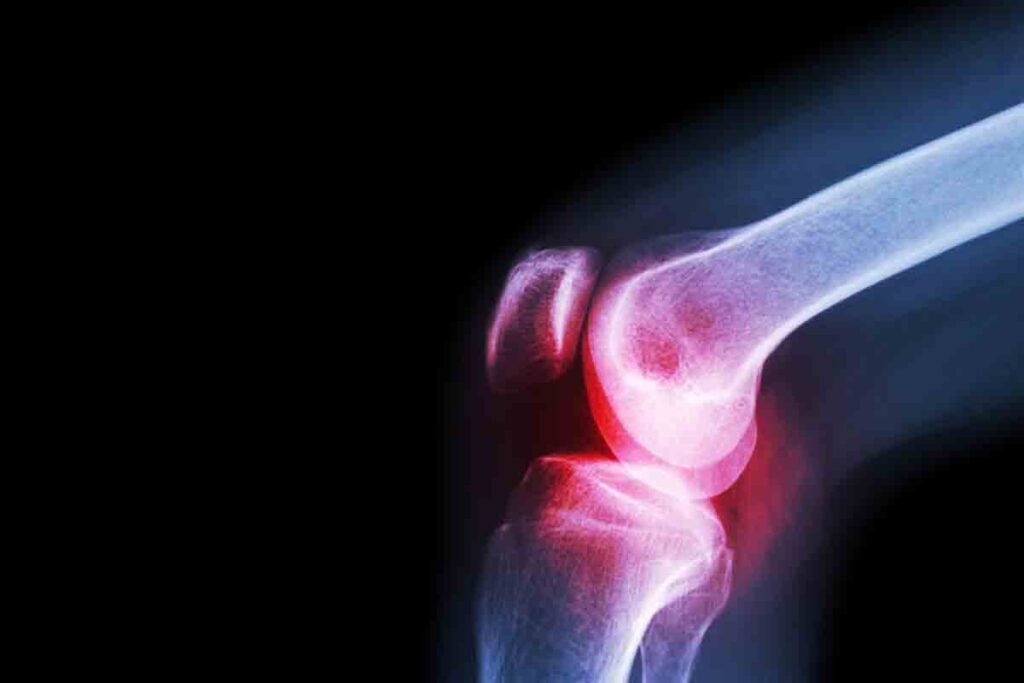

Imaging Studies for Bone Marrow Assessment

Imaging studies help us see the bone marrow and tissues around it. We use X-rays, CT scans, MRI, and PET scans to find any problems. These studies help us see bone lesions, fractures, or cancer.

For instance, an MRI can show detailed images of the bone marrow. This helps us find changes in the marrow’s structure or composition.